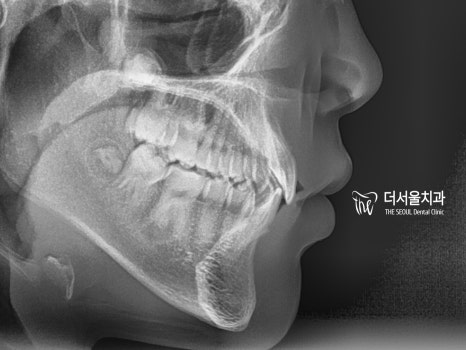

이와 더불어 2급 부정교합도

함께 관찰되고 있었기 때문에

성장판 확인을 거친 후!

【 인비절라인 교정 진단 】

2급 부정교합 그리고

앞니 벌어짐을 인비절라인으로

개선을 돕기로 했습니다.